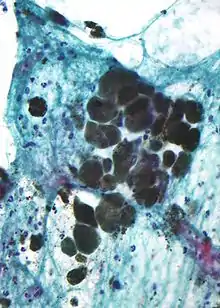

Microscopic appearance

Melanin is brown, non-refractile, and finely granular with individual granules having a diameter of less than 800 nanometers. This differentiates melanin from common blood breakdown pigments, which are larger, chunky, and refractile, and range in color from green to yellow or red-brown. In heavily pigmented lesions, dense aggregates of melanin can obscure histologic detail. A dilute solution of potassium permanganate is an effective melanin bleach.[45]